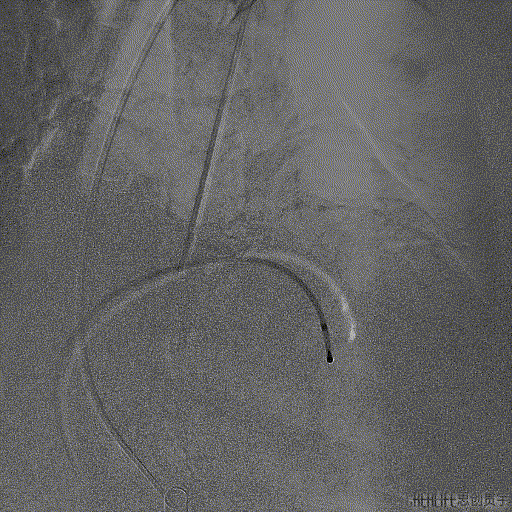

SENTINEL捕获并移除的碎片

张小卫教授在SENTINEL成功应用后表示:脑卒中是所有结构手术中一直非常头疼的问题,目前阶段会优先考虑在高龄,动脉硬化严重的TAVR以及二尖瓣狭窄患者中应用SENTINEL抗栓塞脑保护装置,其通过性和容忍度都非常优秀。该例患者虽然解剖复杂困难,但是整个操作相对简单仅用时3min即顺利成功植入,并且捕获到血栓,对于结构手术的安全保护作用意义深远。